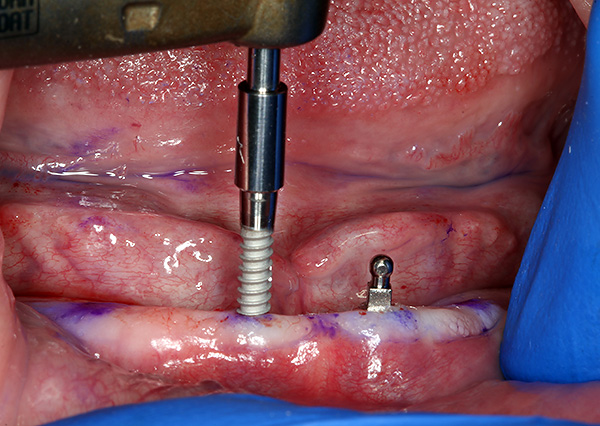

Para instalar mini-implantes, basta fazer um orifício na membrana mucosa até o osso nos locais selecionados. O sangramento leve que começa após uma punção não interfere com outras manipulações.

Através dos orifícios preparados, um orifício é então perfurado no osso no qual o implante é parafusado.Nesse caso, o orifício é feito com um diâmetro menor que o diâmetro da rosca do implante, e a própria rosca durante a instalação não apenas fixa rigidamente o implante, mas também aperta o próprio osso. Graças a isso, o mini-implante pode ser carregado imediatamente com uma prótese.

O procedimento para instalar um mini-implante leva de 5 a 10 minutos e é realizado sob anestesia local. Ao mesmo tempo, o paciente não sente dor ou sensações desagradáveis; portanto, na maioria das vezes, as pessoas respondem bem à instalação desses implantes.